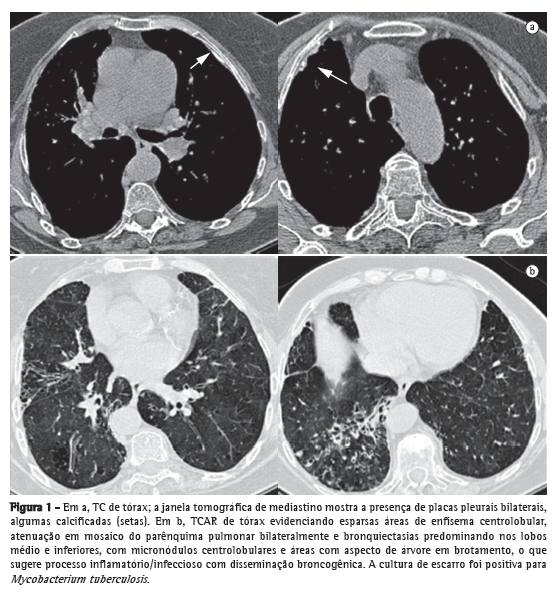

Apresentava à TCAR de tórax áreas de enfisema centrolobular, atenuação em mosaico bilateralmente, bronquiectasias nos lobos superior direito, médio e inferiores, nos quais se notavam ainda micronódulos centrolobulares e áreas com padrão de árvore em brotamento, sugerindo processo inflamatório/infeccioso com disseminação broncogênica. A janela de mediastino mostrava a presença de placas pleurais bilaterais, algumas calcificadas (Figura 1).

A cultura de escarro foi positiva para Mycobacterium tuberculosis. Foi iniciado tratamento específico, e a paciente segue em acompanhamento ambulatorial.